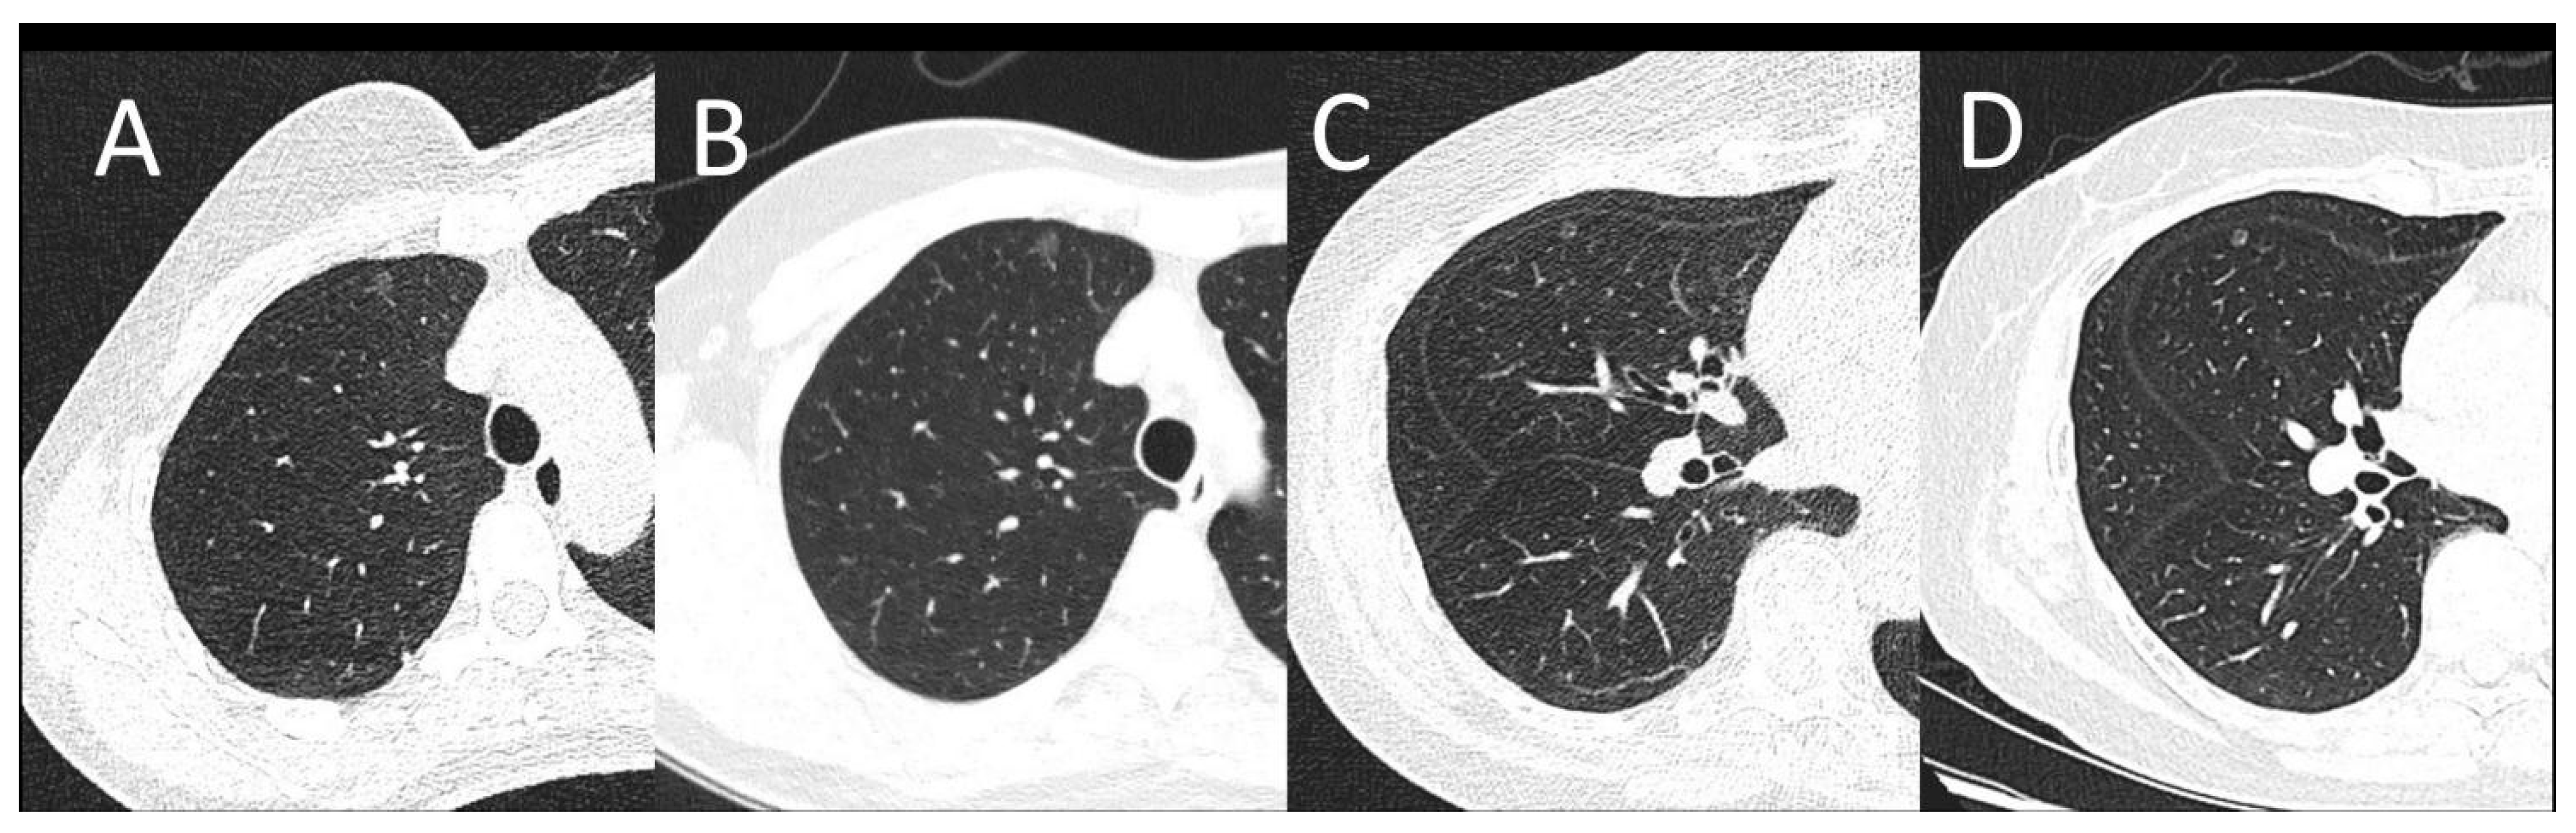

There is no detection efficacy difference between the SDCT and LDCT groups. The CT values of recognizable nodules in the LDCT group ranged from −853.9 HU to 7.2 HU, and nodule sizes ranged from 3.8 mm to 15.5 mm. While the CT values of identifiable nodules in the SDCT group ranged from −753.9 HU to 6.2 HU, and their sizes varied from 3.8 mm to 15.5 mm. No significant difference was observed between LDCT and SDCT in terms of the diameter or CT values of pulmonary nodules (p > 0.05) (Table 3). The identification performance of small pulmonary nodules of LDCT and SDCT is shown in Figure 2.

Figure 2.

(A,B): A female patient with a BMI of 20.31 kg/m2. A subpleural pulmonary nodule was shown on LDCT (A) and SDCT at the same location as A (B). (C,D): A female patient with a BMI of 24.91 kg/m2. One pulmonary nodule can be seen on LDCT (C) and SDCT at the same location as C (D). Images of both protocols can clearly show the lesion. The image noise was appreciably increased on LDCT images, however, there was sufficient contrast between the nodule and the adjacent lung tissue for lesion identification.